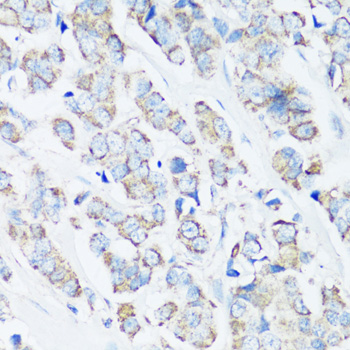

Immunohistochemistry of paraffin-embedded human lung cancer using SRC antibody.

Immunohistochemistry of paraffin-embedded human breast cancer using SRC antibody. |